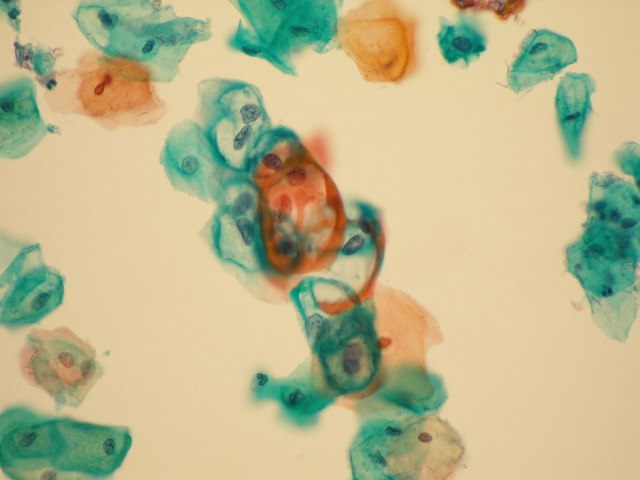

- (3)細胞診判定および診断

- 病変部の擦過や注射針による穿刺吸引物、喀痰、尿、体腔液(胸水、腹水など)などの検体から標本を作製し顕微鏡で観察して、がん細胞などの有無を確認する検査です。組織診断と異なり、非侵襲性で迅速かつ簡便で、ある程度の反復検査が可能です。細胞診標本は細胞検査士が鏡検し報告しますが、異型細胞がみられた症例に関しては細胞診専門医が最終的な診断を確定します。特別な症例を除き報告までに2日程度を要します。

細胞診材料

異型細胞(HPV感染細胞)